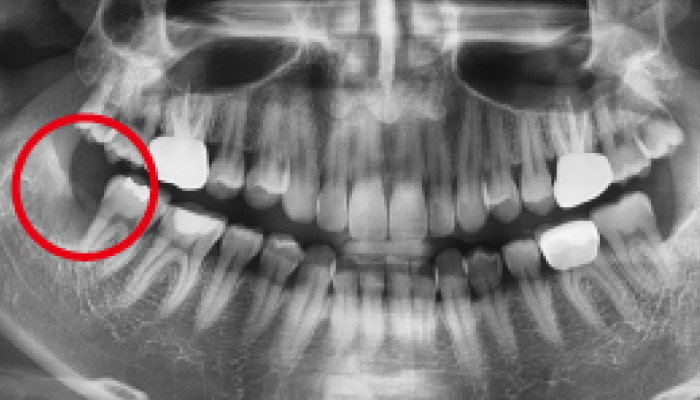

스케일링 이런분께 추천드립니다!

다음과 같은 경우 스케일링 치료를 통해 건강한 치아로 회복하실 수 있습니다.

• 잇몸이 붓고 피가 나며

냄새가 나는 분

• 임플란트 주위염

예방을 원하는 분